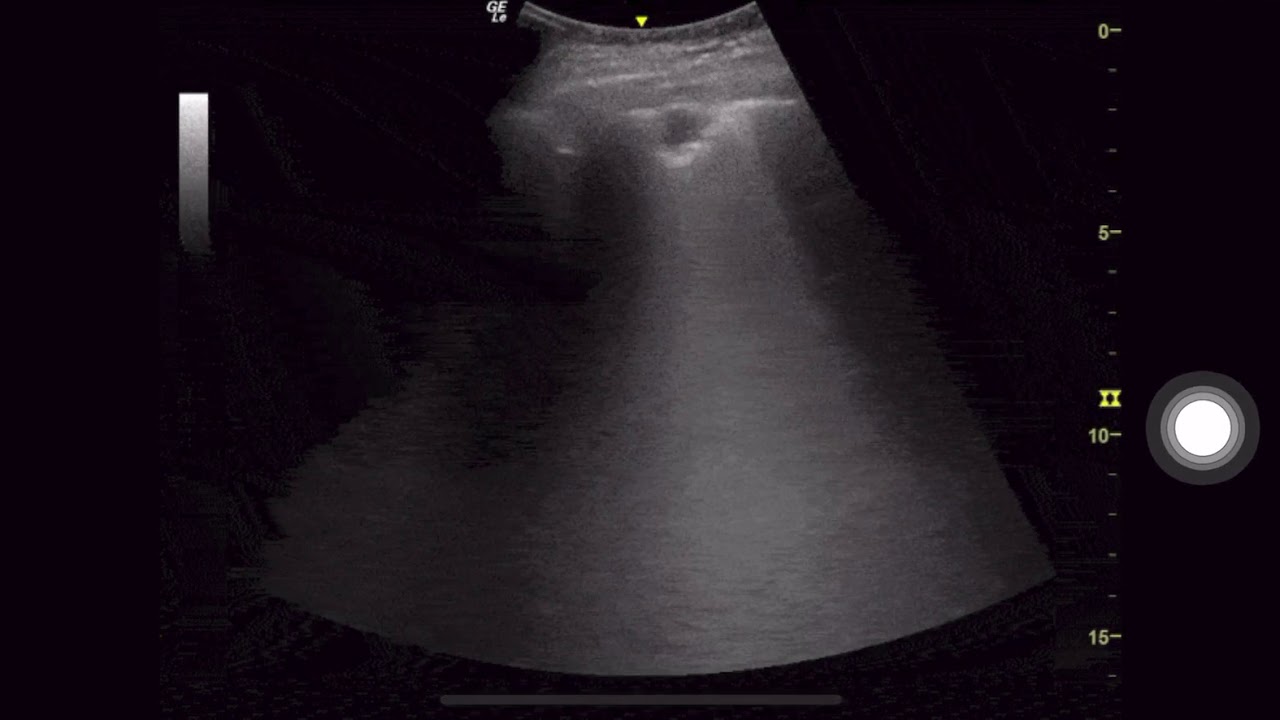

Subpleural Consolidation in COVID 19 Pneumonia

In this video we discuss the sonographic characteristics of a sub-pleural consolidation in the setting of a patient who was ultimately diagnosed with COVID-19.